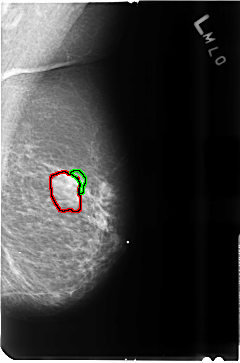

FILE: B_3515_1.LEFT_MLO.OVERLAY

TOTAL_ABNORMALITIES 2

ABNORMALITY 1

LESION_TYPE MASS SHAPE ROUND-OVAL MARGINS CIRCUMSCRIBED-OBSCURED

ASSESSMENT 4

SUBTLETY 4

PATHOLOGY BENIGN

TOTAL_OUTLINES 1

BOUNDARY

ABNORMALITY 2